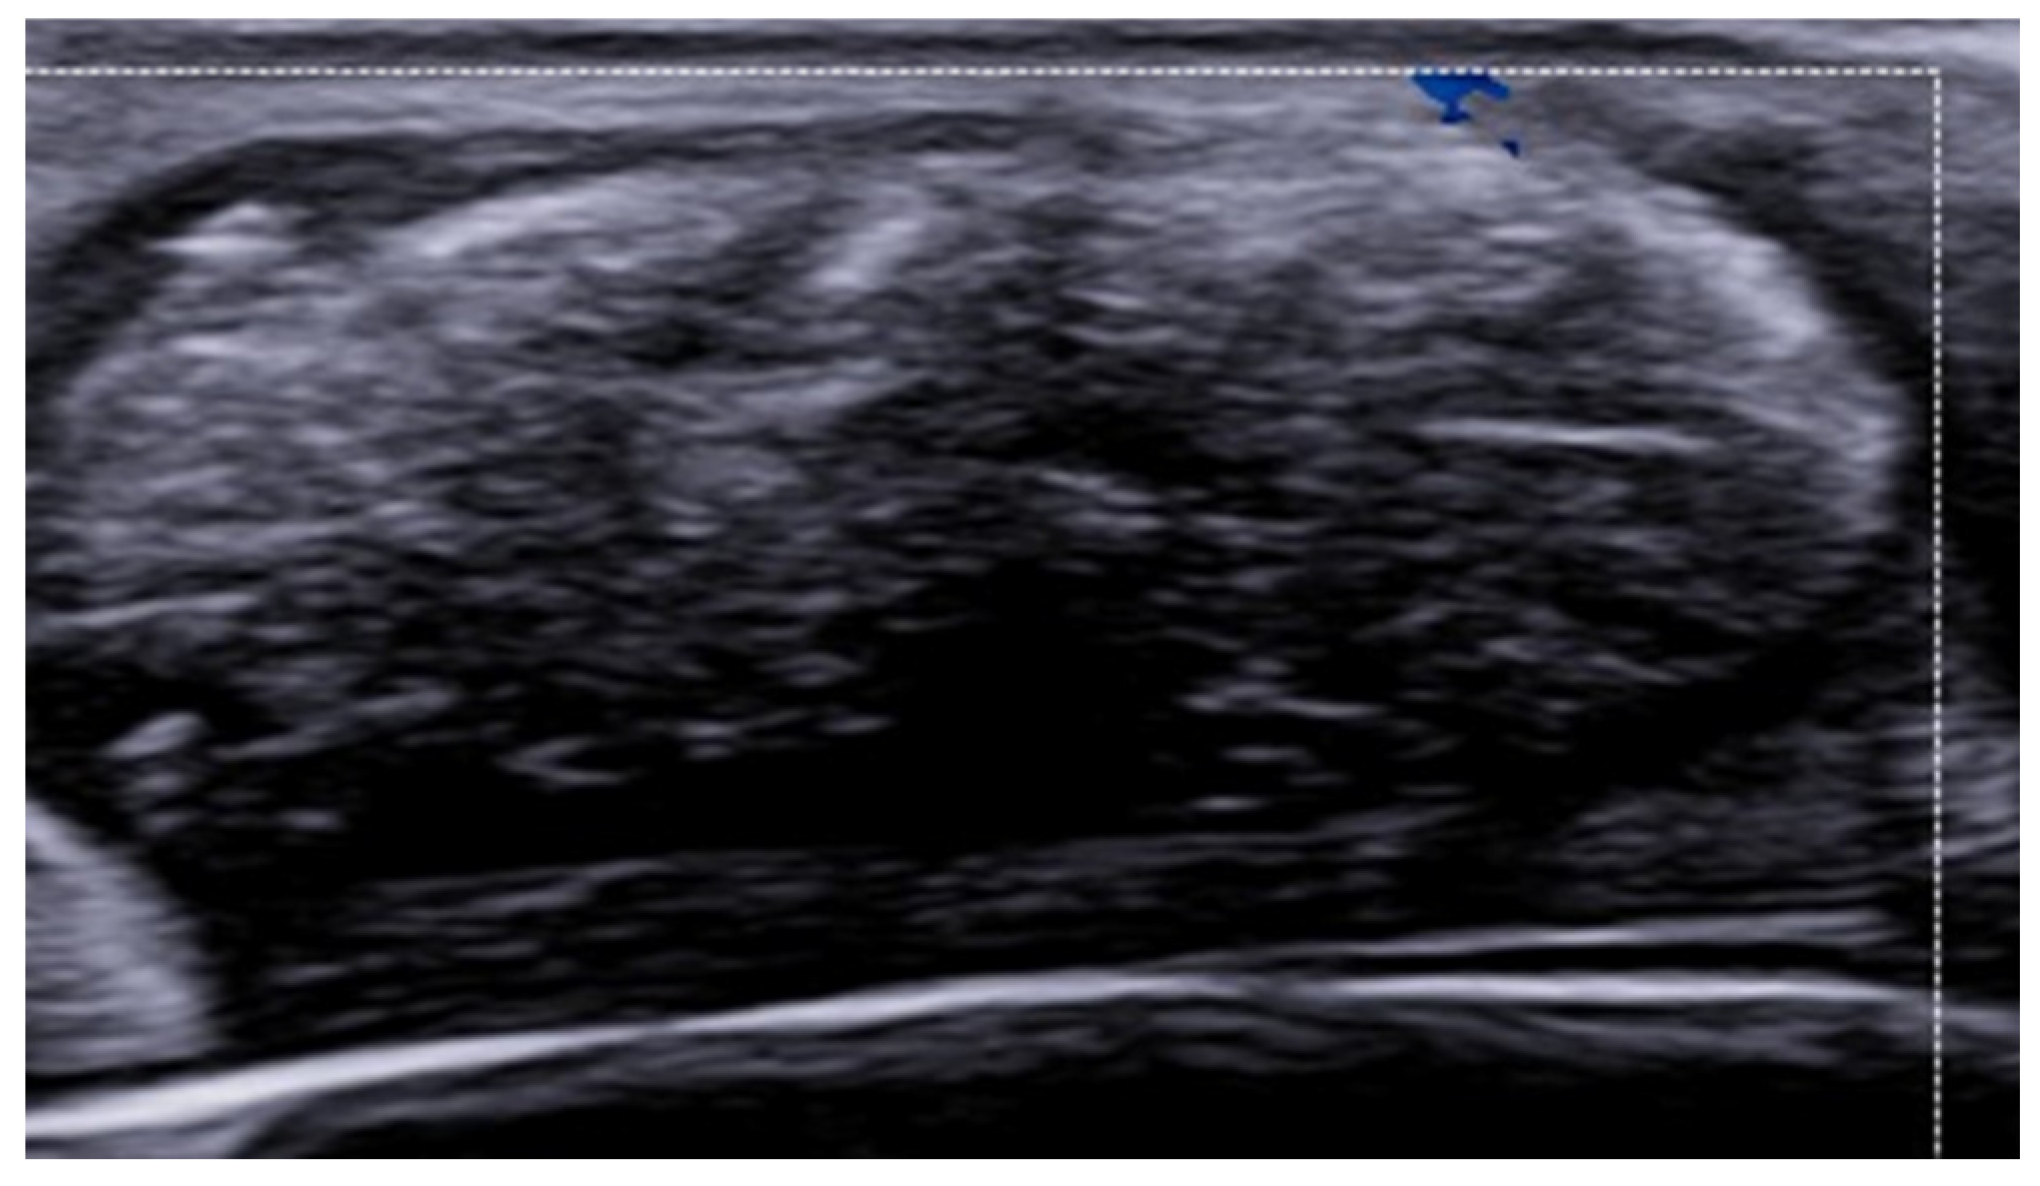

3. Inflammatory Dermatoses